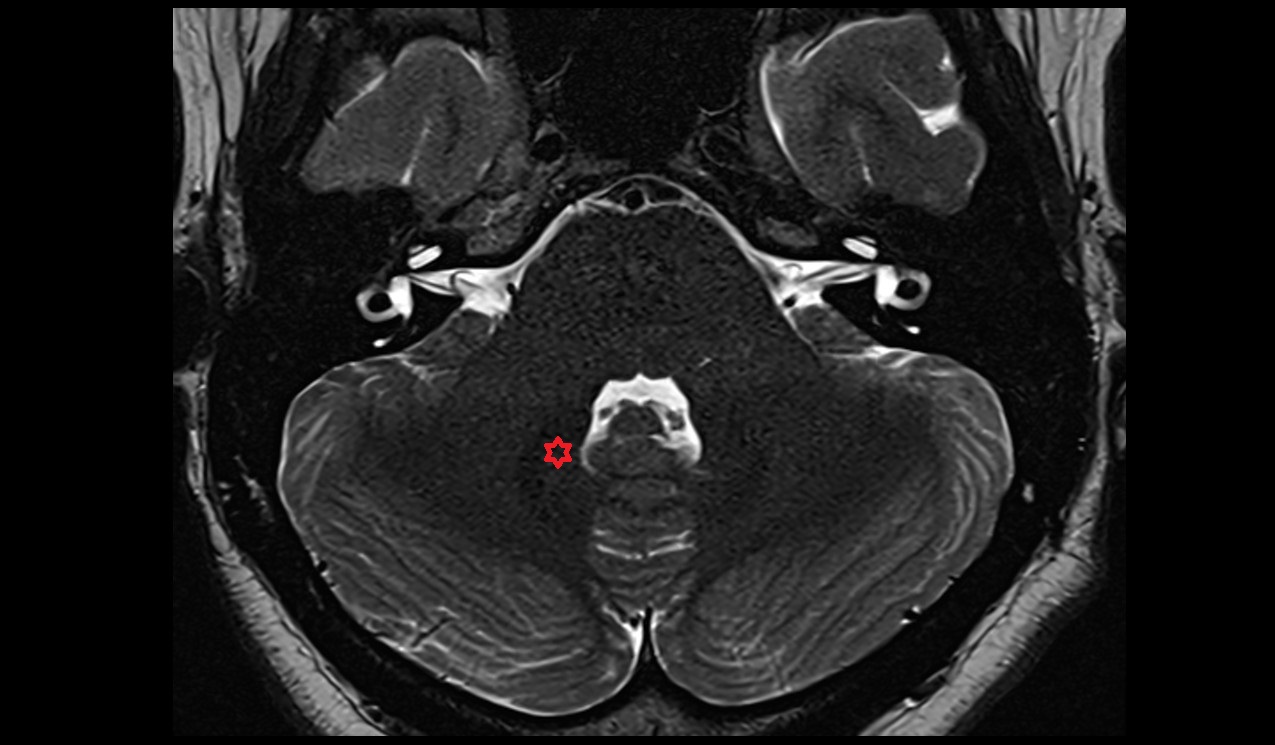

- Cerebellum

- Flocculus

- Cerebellar tonsil (H IX)